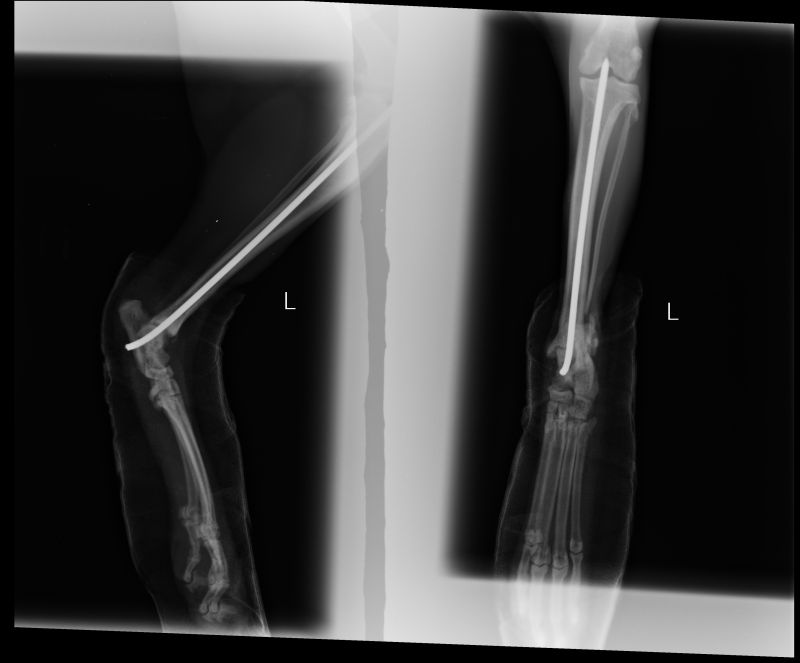

Abnormal Pathology on your pet

Shown on x-ray images which we have taken over the years.

Some interesting patient cases